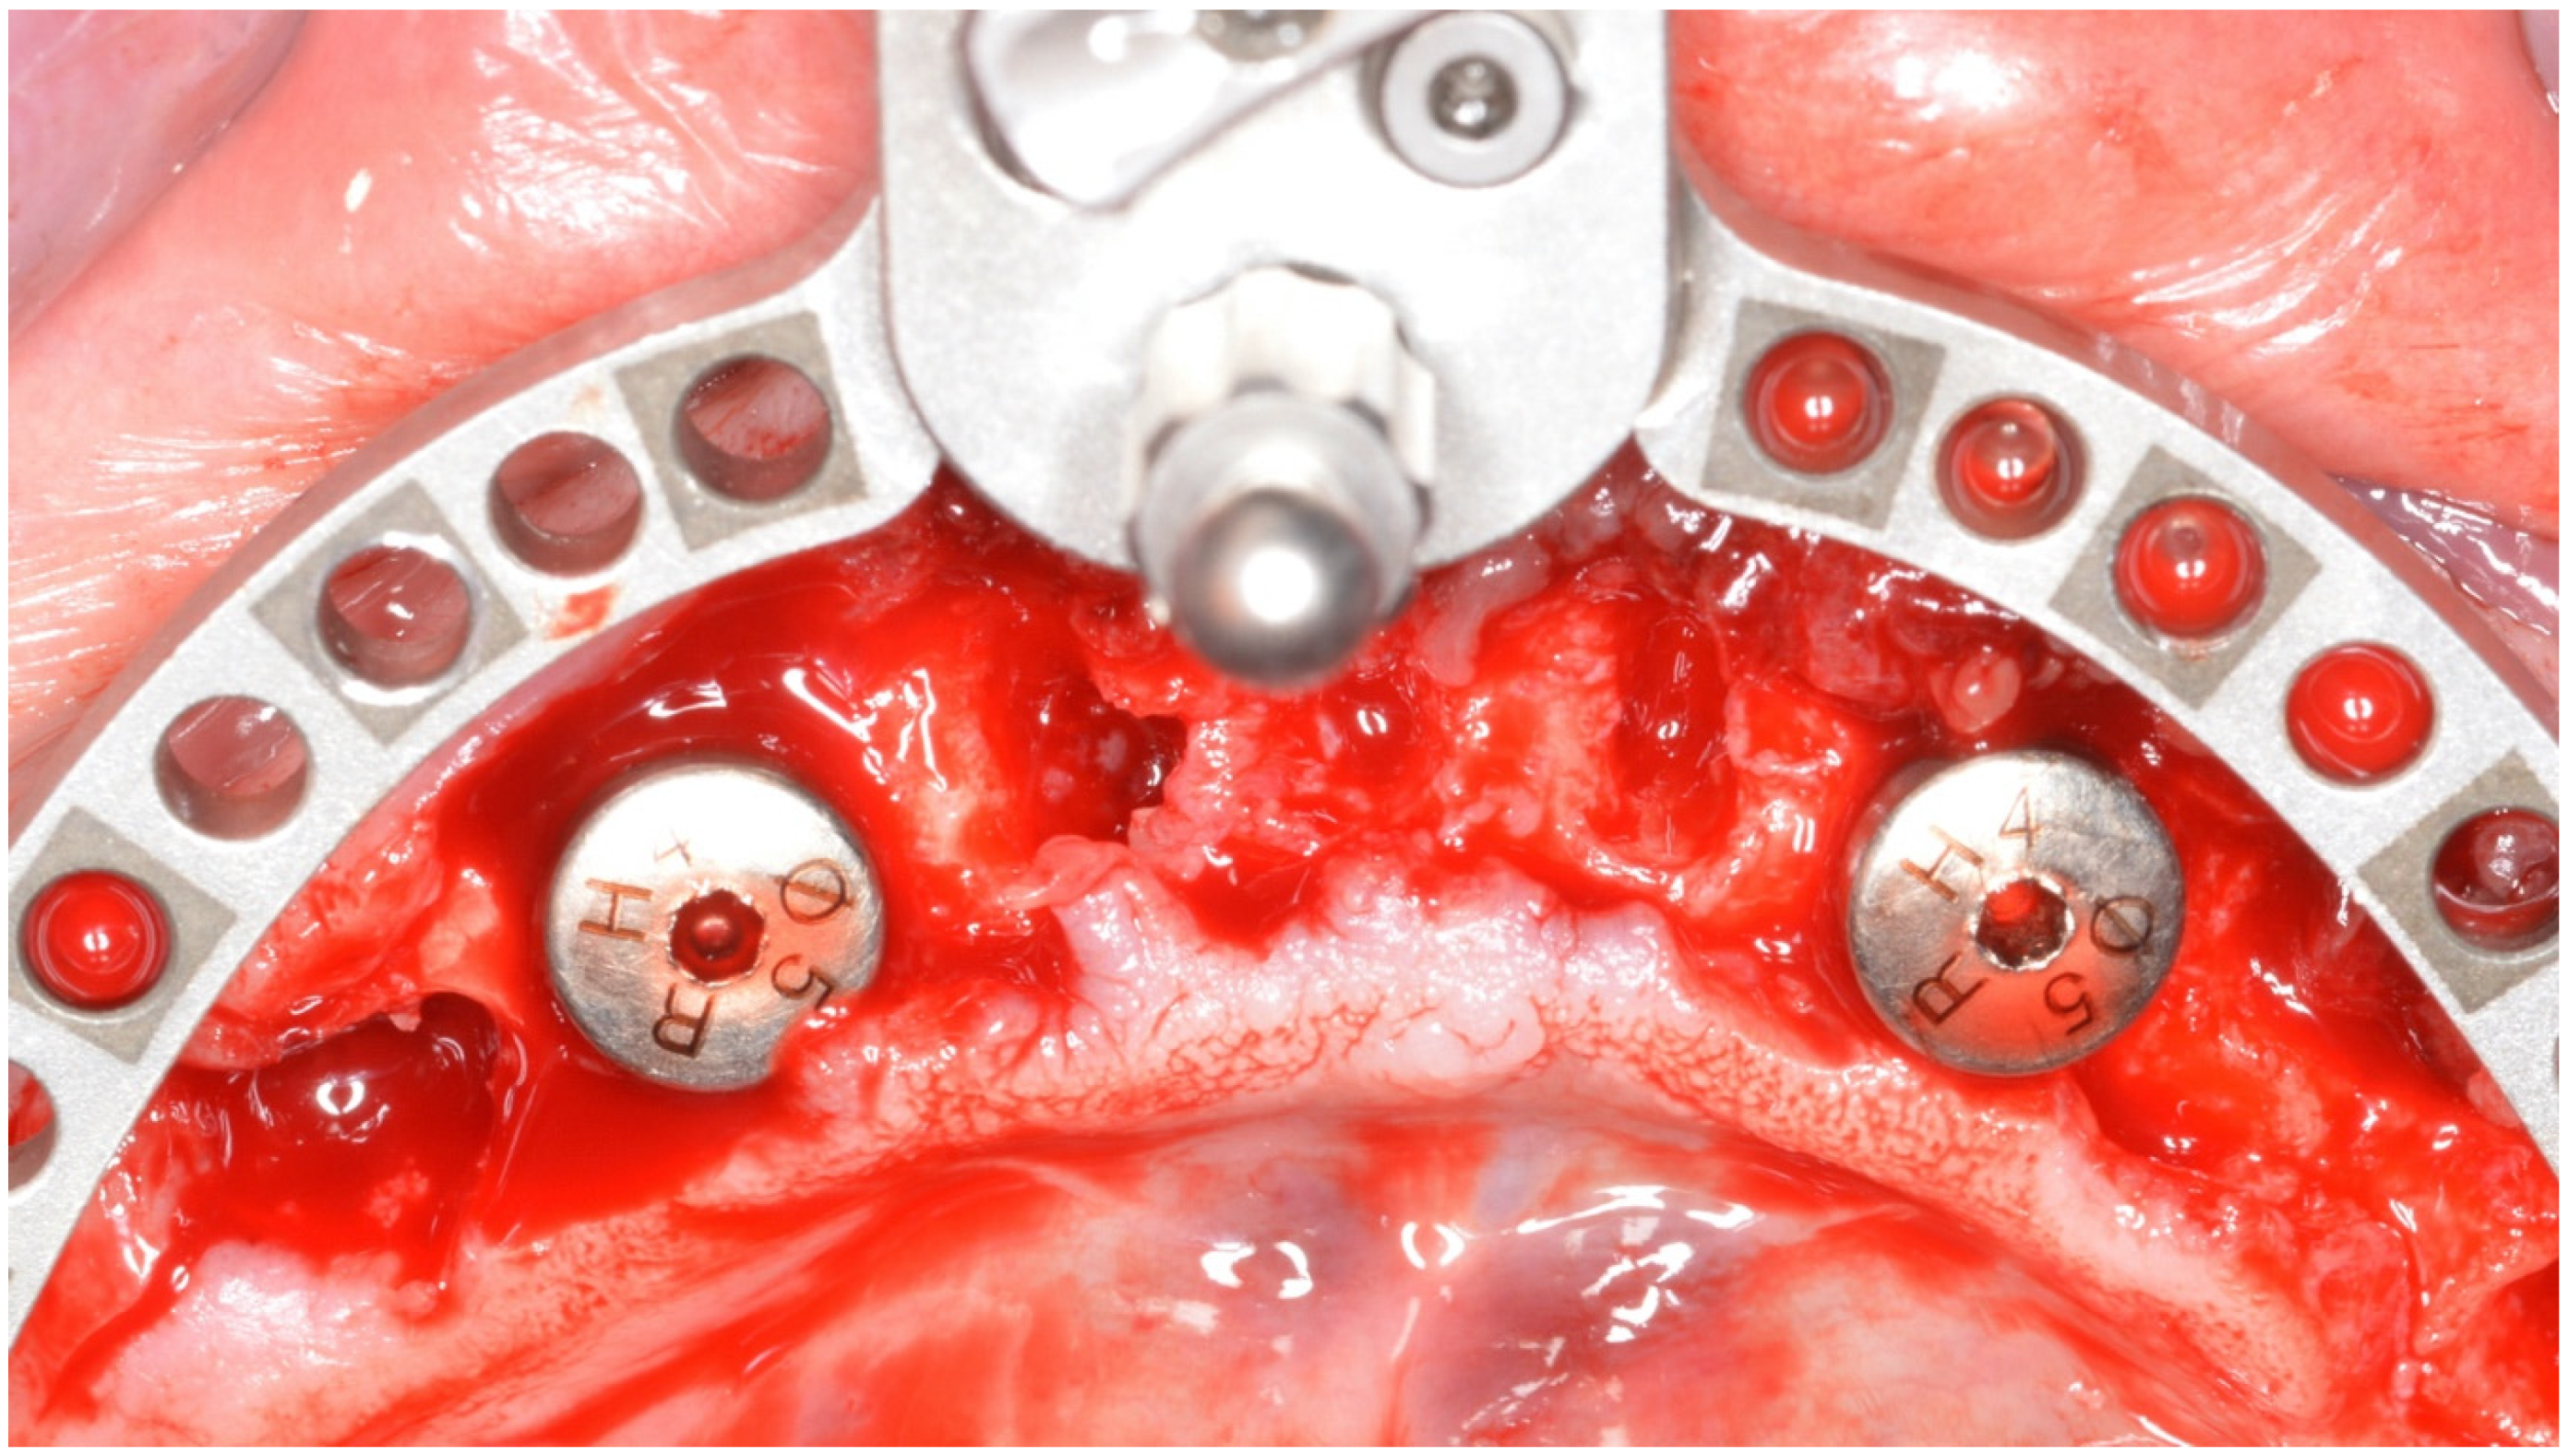

2. Materials and Methods